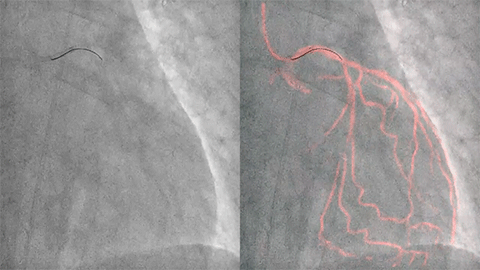

StentBoost Live ofrece una visualización en vivo, instantánea y mejorada para posicionar e implementar globos, stents y otros dispositivos durante los procedimientos intervención coronaria percutánea (PCI). Nuestra Dynamic Coronary Roadmap exclusiva le ayuda a navegar por las tortuosas arterias coronarias de manera eficiente y precisa.

Ofrecemos una gama de herramientas clínicas avanzadas, como VesselNavigator, EchoNavigator y HeartNavigator para la orientación por imágenes 3D en vivo. Nuestra exclusiva Dynamic Coronary Roadmap (hoja de ruta coronaria dinámica) le ayuda a navegar por las arterias tortuosas de manera eficiente y precisa. Cada disciplina quirúrgica puede beneficiarse de herramientas avanzadas de fusión de imágenes que pueden mejorar la confianza, la eficiencia y la precisión durante los procedimientos.